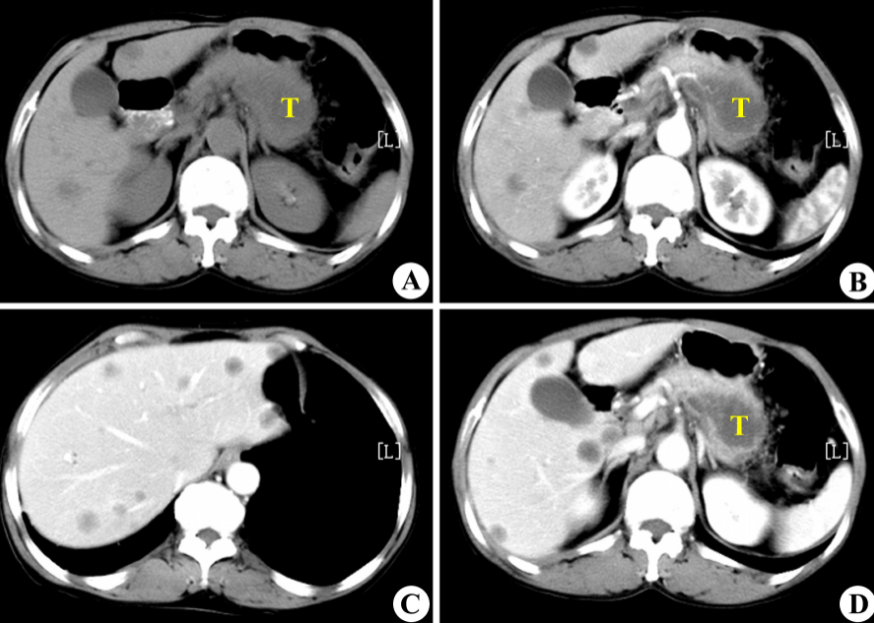

在前面提到的阿里所使用的PANDA模型中,最重要的一個技術,就是一種叫做**“圖像配準”**的技術,將對比增強CT上的病變標註“複製”到非對比CT圖像上。

用直觀的語言來描述,這種做法就是:先找兩張CT圖片,其中一張是普通CT,另一張是增強CT,之後,PANDA通過將兩張CT“重疊”在一起的辦法,來將增強CT上的病變區域準確地映射到普通CT的相應位置上。

具體來説,在第一階段,PANDA會使用nnU-Net模型——一種特定的深度學習架構,精確地識別和分割出胰腺的區域。就相當於用畫筆勾勒出胰腺的輪廓。

在第二階段,一旦胰腺區域被定位和分割出來,PANDA的聯合分割和分類網絡,就會判斷這些區域是異常的還是正常的,如果異常,就要找出相應的病變區域。

第三階段(Stage 3)- 病變亞型分類:在檢測到病變之後,這個階段的目標是對這些病變進行更細緻的分類,比如區分不同類型的腫瘤或病變。